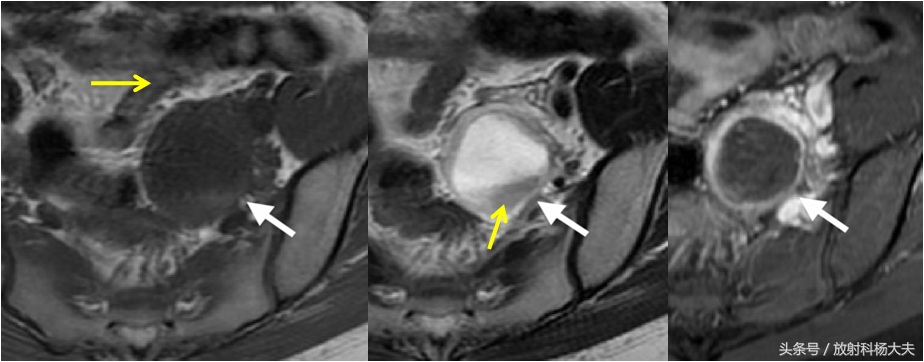

那为何,住院医要拿出来读这个呢?得先看下片子。住院医担心的是这个囊的壁比较厚,有强化,而且囊液不单纯。

左图黄箭为肠管,中间图黄箭为陈旧出血

核磁上怎么诊断呢?黄体囊肿尝尝表现为单发,直径大于2.5cm,小于6cm,壁较薄—可表现为T1WI稍高、T2WI稍低信号、明显强化。没有经验的年轻医生可能看到壁有强化,就担心是恶性的。但黄体囊肿是例外,这是因为黄体化细胞层血运丰富,有时候可伴有少量液体渗出以及出血。不用担心,这种囊肿,假如一切顺利,比如没有发生意外的撞击,都是可以消退的。